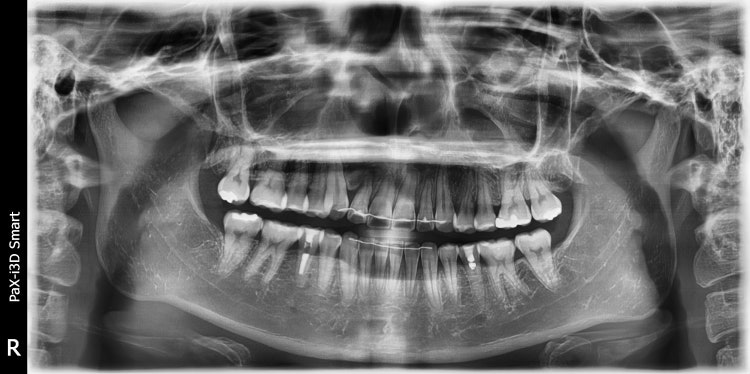

환자분과 방향이나 위치가 조금 다르지만 어쨌든 오른쪽 위 송곳니 매복인 성인 환자입니다.

환자분도 약간정도 있겠지만 이 환자는 중심선이 오른쪽으로 많이 틀어져 있고 교합이 약간 밀려들어가 있는 상태였습니다.

후방부(환자분의 경우도 사랑니를 뽑고 치아를 이동시켜줄 방향이죠)로 치아들을 이동시켜서 공간을 만들고 배열해 주었습니다.

윗니 하나 없어 보이는 것이 사는데는 전혀 지장없습니다. 그렇지만 심미적인 것이나 보철로 했을때 기능적으로 달라질 것이 있는지는 잘 들어보시고 판단하시기 바랍니다. 결국 결정은 본인 몫일것 같습니다.